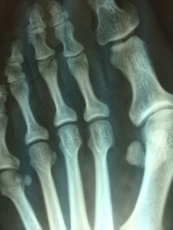

En Clínica del Pie Basas tratan a pacientes de todas las edades, ofreciendo la información que necesitan para tomar buenas decisiones sobre su pie. Podología deportiva, tratamiento del pie diabético, eliminación definitiva de callos, cirugía en juanetes, fascitis, dedos en garra, uñas incarnadas o espolones son algunos de los servicios que realizan en esta clínica, una referencia en Salamanca.

El doctor Felipe Basas, en su clínica del Paseo del Romero, indica que uno de los servicios que ofrecen es el estudio biomecánico de la pisada y del pie en posición estática y dinámica "para determinar si hay una mala pisada que puede provocar lesiones en la rodilla, la cadera o la columna".

Teniendo en cuenta que más del 75 por ciento de las personas experimentarán problemas de los pies en un momento u otro en su vida, es fundamental mantenerlos en perfecto estado. Sin embargo, el cuidado de los pies debe empezar desde la infancia. El doctor Basas explica que los padres llevan a sus hijos periódicamente a las revisiones del pediatra, "pero también es necesario revisiones del podólogo para detectar si un pie puede tener una patología en el futuro y para asegurar un correcto crecimiento".